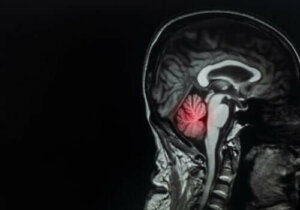

Tipuri de tratament pentru metastazele cerebrale

În articolul de azi, îți vom explica tot ceea ce trebuie să știi despre metastazele cerebrale, inclusiv care sunt principalele tipuri de tratament pentru acestea.

Metastazele cerebrale reprezintă aproximativ 90% din cazurile de tumori cerebrale. Tratarea acestora constituie o adevărată provocare pentru medici.

Metastazele cerebrale constituie aproximativ 90% din cazurile de cancer la creier. Este esențial ca pacienții să obțină un diagnostic corect cât mai curând posibil pentru a putea stopa evoluția bolii.